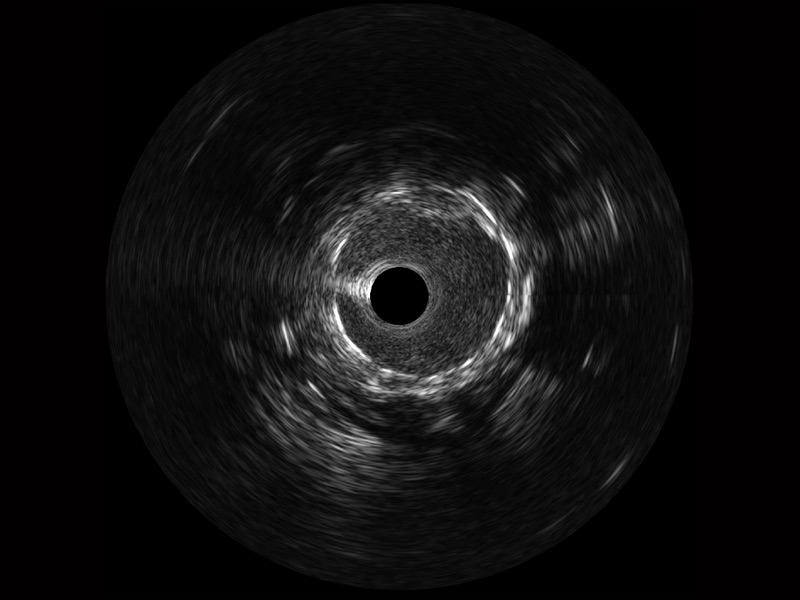

玖鼎集团宽频IVUS图像

传统IVUS图像

对比传统IVUS导管成像,玖鼎集团宽频IVUS图像的近场支架梁显影更细腻,远场中膜外血管仍清晰可辨,兼顾远中近,兼顾分辨力与穿透深度